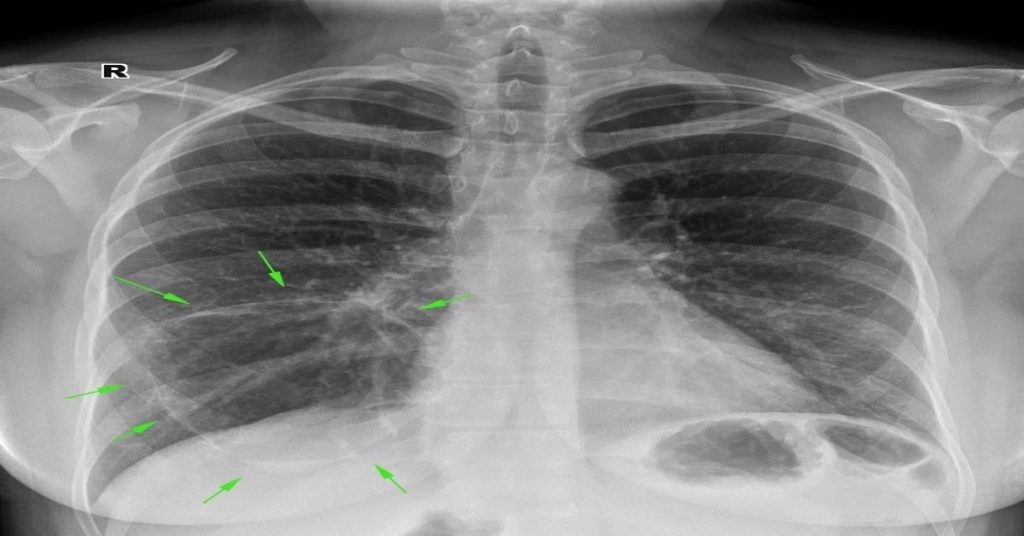

Tanı genellikle klinik muayene ve akciğer grafisi ile konur. Şüpheli durumlarda kan testleri ve ileri görüntüleme yöntemleri kullanılır. Özellikle risk grubundaki hastalarda aspirasiyon pnömonisi hızlı ilerleyebilir. Bu nedenle erken müdahale hayati önem taşır.

Tanı için doktor muayenesi ve akciğer grafisi kullanılır. Şüpheli durumlarda kan testleri veya ileri görüntüleme yöntemleri eklenebilir. Erken teşhis, tedavi başarısını artırır. Risk grubundaki kişiler yakından izlenmeli ve önleyici tedbirler almalıdır. Bu, komplikasyonları azaltır.